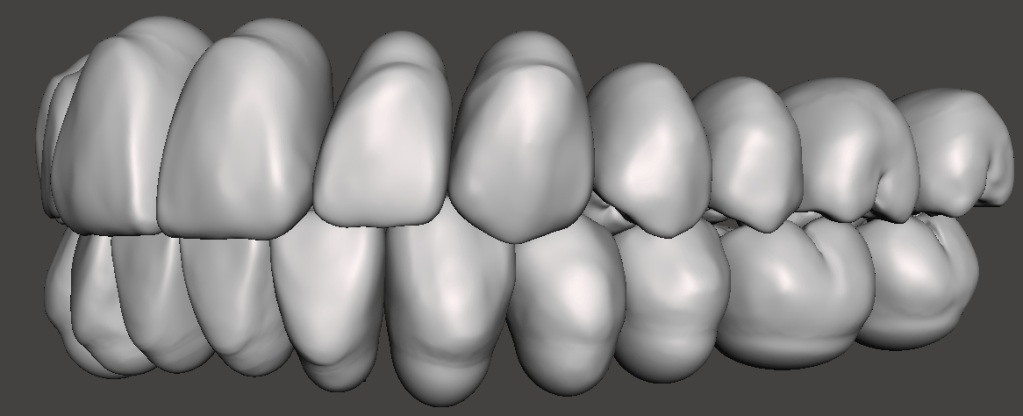

Ideal Occlusion

The ideal shape of the front teeth is with centrals longer than the laterals and the canines are at the same level as the centrals. This will will give you a positive smile line